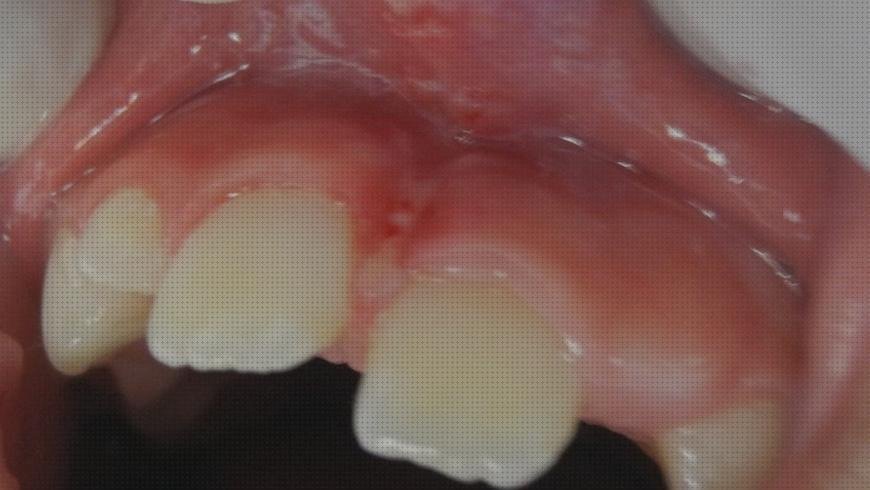

Una vez anestesiada la zona, se método un corte lavado del ligamento con un bisturí eléctrico y se coagulan los puntitos que sangran y ya es. Del filo quedará una pequeña herida con manera de rombo de no bastante más de un centímetro. Esta puedes bordar con puntos sueltos que luego se caerán, o se puede dejar que cure ella sola, como cualquier marca que te puedas hacer en el cuerpo. Generalmente no se están poniendo puntos (aunque obedece del nefrólogo) y se aplica una crema antibiótica después de terminar el corte. La tendencia de no poner puntos es para minimizar el dolor del postoperatorio. Las dos posibilidades son válidas y el resultado atractivo es muy parecido.